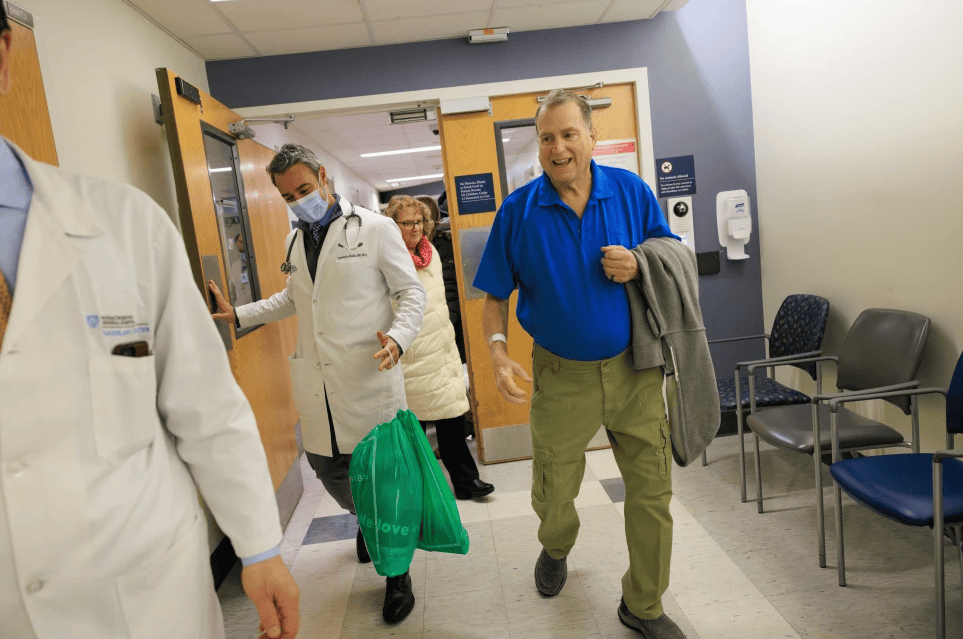

△今年1月,蒂姆·安德鲁斯(右)在美国马萨诸塞州接受基因编辑猪肾脏移植

△当地时间2月1日,接受基因编辑猪肾脏移植后的蒂姆·安德鲁斯(右)

安德鲁斯在移植手术后暂时摆脱透析治疗,创造了基因编辑猪肾脏在人体内存活的最长纪录。尽管采用了基因编辑与强效免疫抑制方案,他体内仍发生移植器官排斥反应。据院方介绍,本月23日晚,医生为其实施手术摘除猪肾脏。安德鲁斯表示,排斥反应和药物副作用让他的身体难以承受。